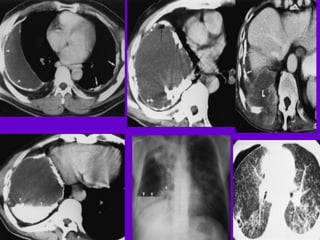

Miliary TB

􀂄 Earliest form of miliary TB is detectable

on HRCT.

􀂄 Coalescing nodules result into patchy

irregular

opacities and HRCT shows this variation

effectively

and has been described as “snowstorm

appearance”.

􀂄 HRCT shows cavitation, which is not

evident on plain

CXR.

􀂄Pleural Effusion

􀂄 CT is sensitive to diagnose and define

even minimal

pleural effusion/pleural calcification.

􀂄 Pleural fluid is seen on inversion

recovery MR

images as areas of increased signal

intensity along

the inner aspects of the chest wall.